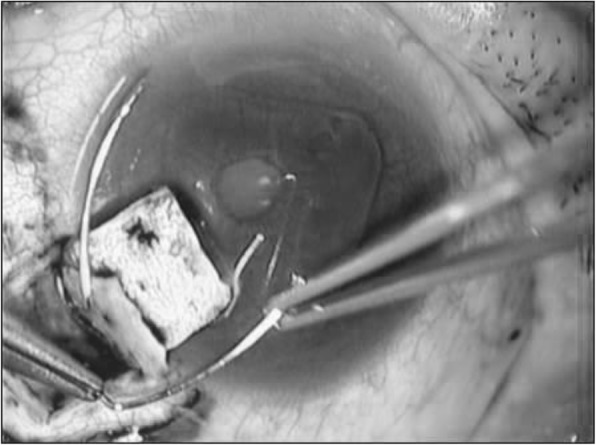

The trabeculotomy technique used in the present study was similar to that reported elsewhere [2], and proceeded as follows: 1. A limbal conjunctival incision was made. 2. A 4 × 4 mm square or triangular scleral double flap was created at the limbus. 3. After identification of Schlemm’s canal, its outer wall was cut with a razor blade and excised with fine scissors. 4. U-shaped probes (Nagata’s trabeculotome probe: Inami & Co., Ltd., Tokyo, Japan) were then inserted into both ends of the opened canal and rotated 90 degrees against the trabecular meshwork and toward the anterior chamber. 5. Rotation of these probes achieved a 120-degree opening of the trabecular meshwork (Fig. 1). 6. In some eyes, one or two sites of 1-mm-diameter sclerostomy through the scleral flap was performed with a punch, as suggested in a previous report [18]. 7. After removal of the inner flap, the scleral flap was closed with four 10–0 nylon sutures. 8. Conjunctival sutures were then placed.

Fig. 1.

Intraoperative photograph of trabeculotomy